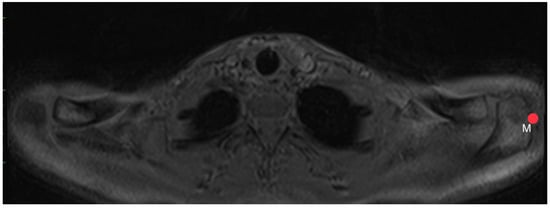

2.4. Acromion Tilt (Figure 6)